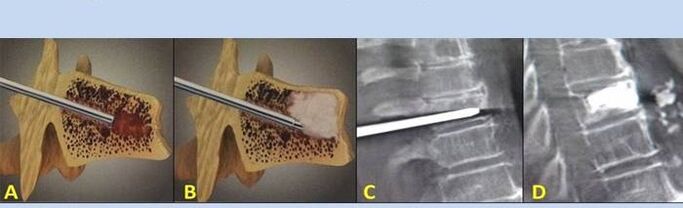

- Nukleoplastia – orno arteko diskoaren muina kentzea. Eragiketak nerbio-bukaeren gaineko presioa arintzen du.

- Zulatze ornoplastia – ornoak egonkortzeko metodoa. Prozeduran zehar, medikuak bizkarrezurreko barrunbeak hezur-zementuz betetzen ditu.